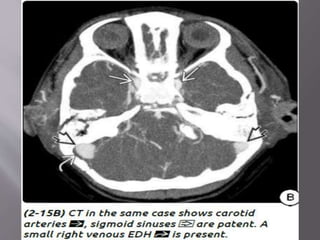

b) Venous EDH- smaller, low pressure, develop

slowly

Most venous EDHs are caused by a skull fracture

that crosses a dural venous sinus and therefore

occur in the posterior fossa near the skull base

(transverse/sigmoid sinus) or the vertex of the

brain (superior sagittal sinus).

b) Venous EDH-smaller, low pressure, develop slowly Most venous EDHs are caused by a skull fracture that crosses a dural venous sinus and therefore occur in the posterior fossa near the skull base (transverse/sigmoid sinus) or the vertex of the brain (superior sagittal sinus). In contrast to their arterial counterparts, venous EDHs can "straddle“ intracranial compartments, crossing both sutures and lines of dural attachment and compressing or occluding the adjacent venous sinuses.